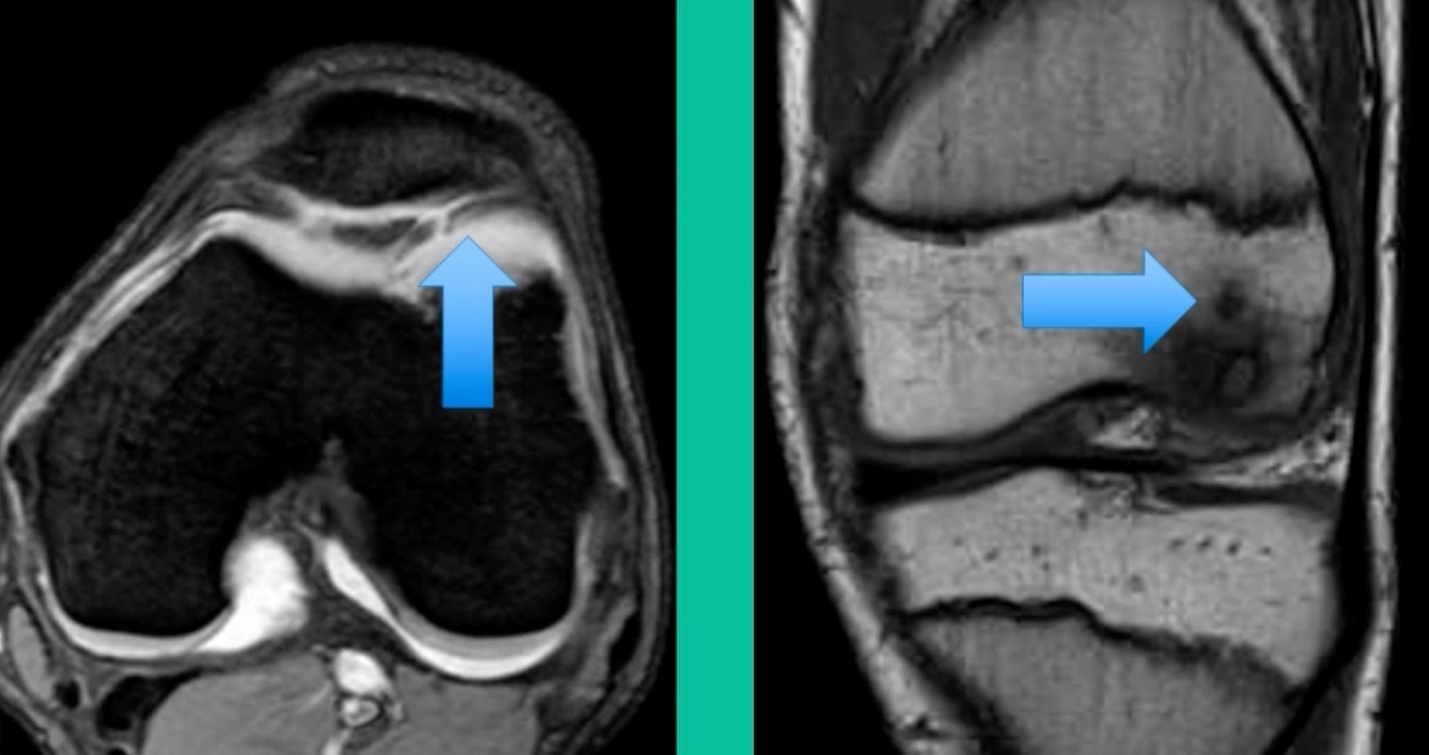

The only other thing to know is about stability. This is probably the most important physiology tenet. This is a biologic problem, because it’s a fracture non-union. But it’s a biomechanical problem because they’ve got a pebble in their shoe when they become symptomatic. So, we talk about the MRIs showing stability. The reality is if they hurt, they probably have microscopic instability. The challenge is if you take a microscopic versus a macroscopically unstable one, the treatment will differ.

Who’s going to heal in the young group? It’s going to be someone who’s much younger. Non-weight-bearing location. Lateral aspect of the medial femoral condyle can often be non-weight-bearing. Smaller lesions, no MRI signs of gross macro-instability, and the absence of sclerosis in cysts. These might heal.

You look at this one, you say, “what are you going to see when you get in there?” This is one when you get in there, you say, I’m not even sure I’m in the right knee because you almost don’t see it. That happens in patients who were painful, but they don’t look macroscopically unstable. Pediatric orthopedic surgeons tend to drill these. These are the ones that I see as failures. I think when you’re talking about something that’s mechanically unstable, it’s hard to understand why drilling would actually make it work without fixation. Even if it’s microscopically unstable.

The challenge is this. This series of patients were populated by early decisions to treat when patients don’t have symptoms. That’s a problem in my mind. Post-Op, they protect their weight-bearing. That’s actually treatment. These are often smaller lesions of the medial femoral condyle. They do really well. That being said, it’s an option. It’s not my option. My option for someone who’s macroscopically unstable is we use biocomposite screws (Figure 4).

This goes back to metallic screw fixation, because this one is macroscopically unstable. That is a fracture non-union. That’s an atrophic non-union. Debride it, curette it, drill it, and thenwe use metal screws because it’s macroscopically unstable.

Worsening over the last two years, has effusions but no locking, and has a large area of involvement that appears unstable. This is the classic fixation. If you can do this, this is the holy grail. Remember, fracture non-union: you elevate it, debride the base, get rid of any unstable fragments, just take them out, and preserve the major fragment. I’ll use a microfracture awl, but most commonly now I’ll use a pick or a pin, and I’ll drill it. I use two to three metal screws. I bury their heads, and then I come back at eight weeks after being non-weight-bearing, and pull the screws out.